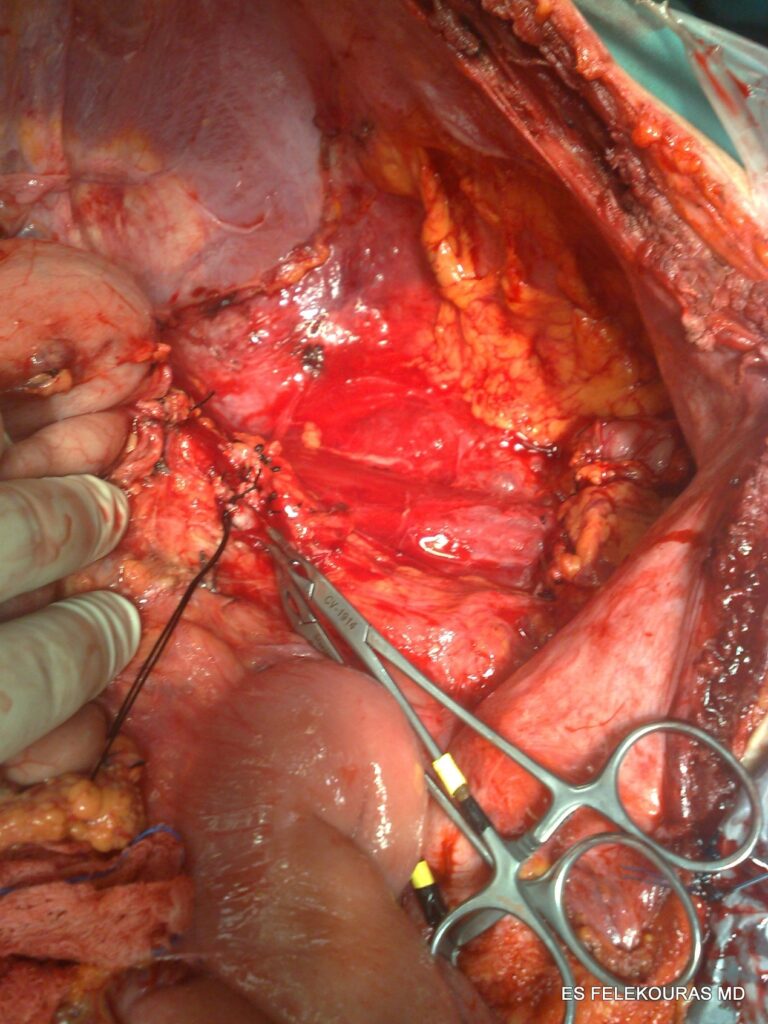

Όταν από τις εξετάσεις αυτές έχουμε υποψία η διάγνωση για ένα ενδοκοιλιακό σάρκωμα τότε θα πρέπει να παραπέμψουμε το ασθενή σε ένα μεγαλύτερο κέντρο με εμπειρία στην θεραπεία των σαρκωμάτων αυτών χωρίς να κάνουμε βιοψία μια και η βιοψία σε αντίθεση με τα οπισθοπεριτοναϊκά σαρκώματα μπορεί να οδηγήσει σε διασπορά (εξαιρούνται εδώ η ενδοσκοπικές βιοψίες για GIST).